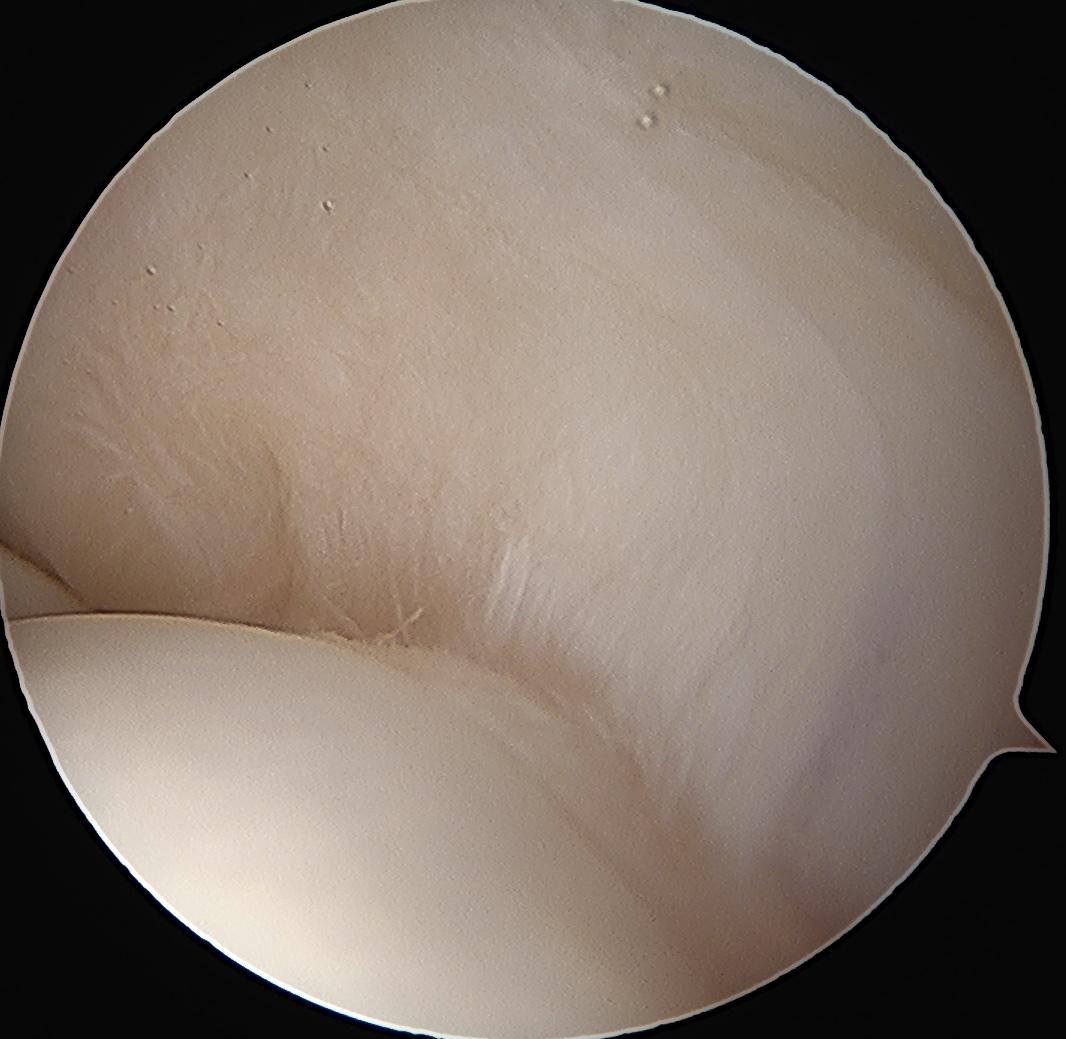

Articular side

Normal insertion of undersurface of the rotator cuff onto the footprint, with camera in glenohumeral joint